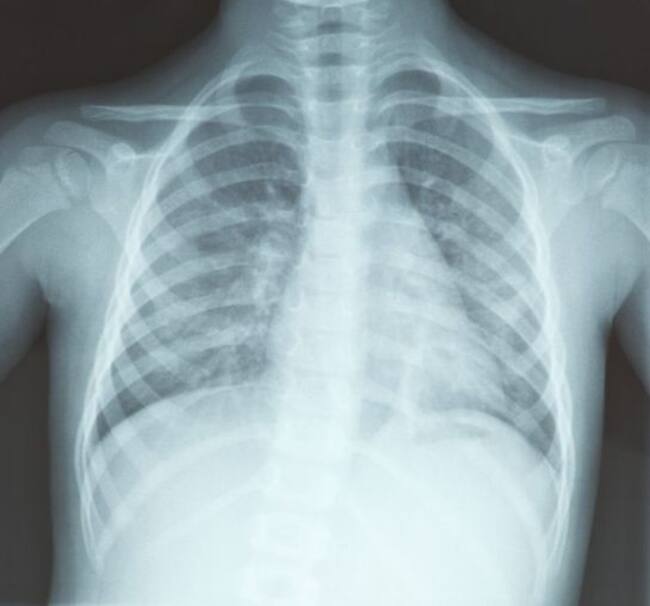

Al presentarse en el hospital el sujeto presentaba fuertes dolores de pecho y tos. Desafortunadamente los doctores al hacer su diagnóstico determinaron que presentaba una neumonía fúnguica pulmonar (que incluso pudo haber sido mortal) lo que podía haber sido causada por la inhalación de esporas y hongos mismos que habitan en el calzado sucio.